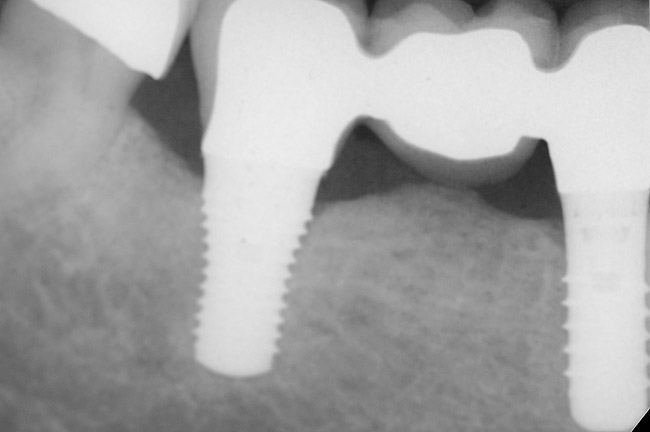

Figure 9 shows the implant placement at the time of extraction and Figure 10 shows the implant-supported fixed bridge. In one surgical procedure, the implants in the Nos. 29 and 31 positions were placed at the time of the extraction of these two teeth. The implants were restored approximately 3 months after placement.

Figure 9  Extraction of teeth Nos. 29 and 31 with immediate implants (Straumann USA, Waltham, MA) placed into the site.

Figure 9

Figure 10  Implants seen in Figure 9 restored approximately 3 months after placement.

Figure 10